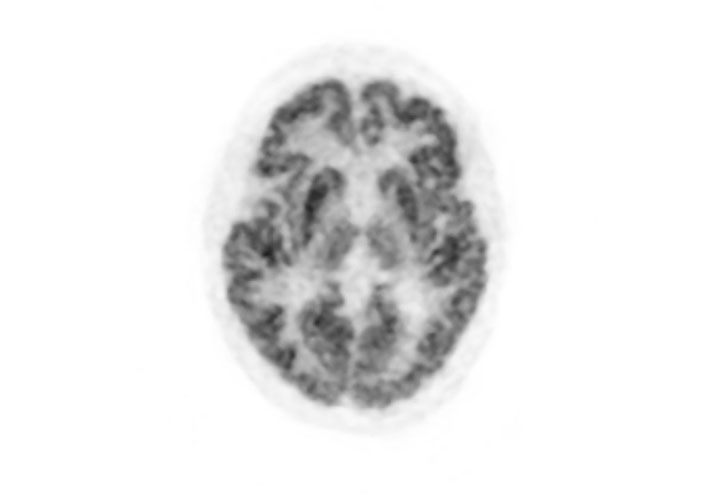

Head / Case1 : FDG

Axial

- Imaging protocol

- Injected dose: 2.87 MBq/kg, 18F-FDG

- Uptake time: 42 minutes

- Scan time: 30 minutes